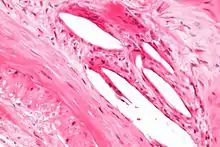

Histology

It is readily visualized with light microscopy in sections of muscular arteries, where it is thick and prominent, and arterioles, where it is slightly less prominent and often incomplete.[1] It is very thin in veins and venules.[1] In elastic arteries such as the aorta, which have very regular elastic laminae between layers of smooth muscle cells in their tunica media, the internal elastic lamina is approximately the same thickness as the other elastic laminae that are normally present.[2]

There is small amount of subendothelial connective tissue between basement membrane of endothelial cells and internal elastic lamina.[3]

Reduplication of internal elastic lamina can be seen in elderly individuals due to intimal fibroplasia, which is part of the aging process.[4]